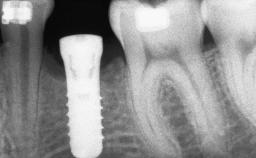

Ridge Preservation and Implant Placement for a Fixed Dental Prosthesis After a Car Accident

# of Implants 4

Type of Implants One-Piece|Reduced-Diameter

Bone Augmentation Horizontal|Simultaneous|Sinus Floor Elevation|Staged